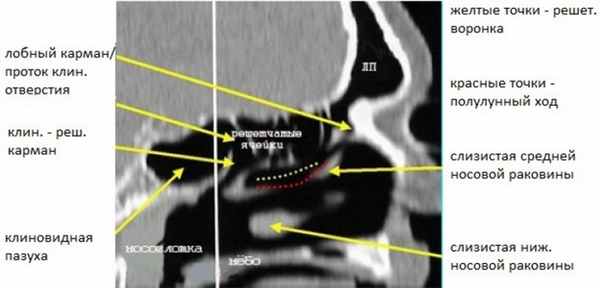

Сошник разделяет два отверстия клиновидных пазух. При хроническом синусите этот комплекс вовлекается реже, потому что в нем более редко встречаются анатомические варианты. Сагиттальная реконструкция ОМК, демонстрирующая искривленный край полулунного хода с нижней складкой слизистой, покрывающей крючковидный отросток показана на рисунке 4. Также здесь виден лобный карман.

Рисунок 4. КТ полости носа. Реконструированное сагиттальное изображение ОМК демонстрирует искривленный край полулунного хода с нижней складкой слизистой, покрывающей крючковидный отросток. Виден также лобный карман/проток.